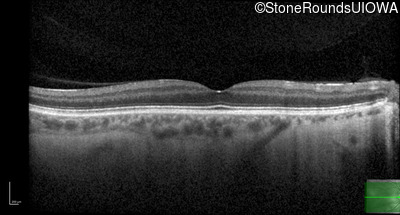

Age at visit: 31 years

OD OS

This 31 year old man has had poor acuity since early childhood.